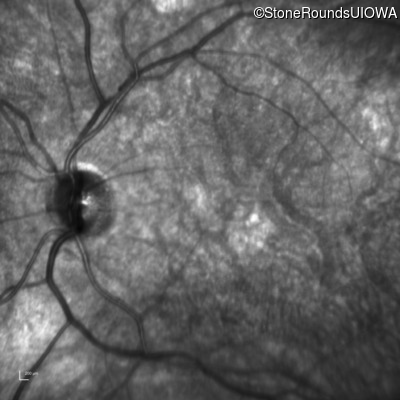

Infrared Fundus Photograph - Left - 20/100

Exemplar